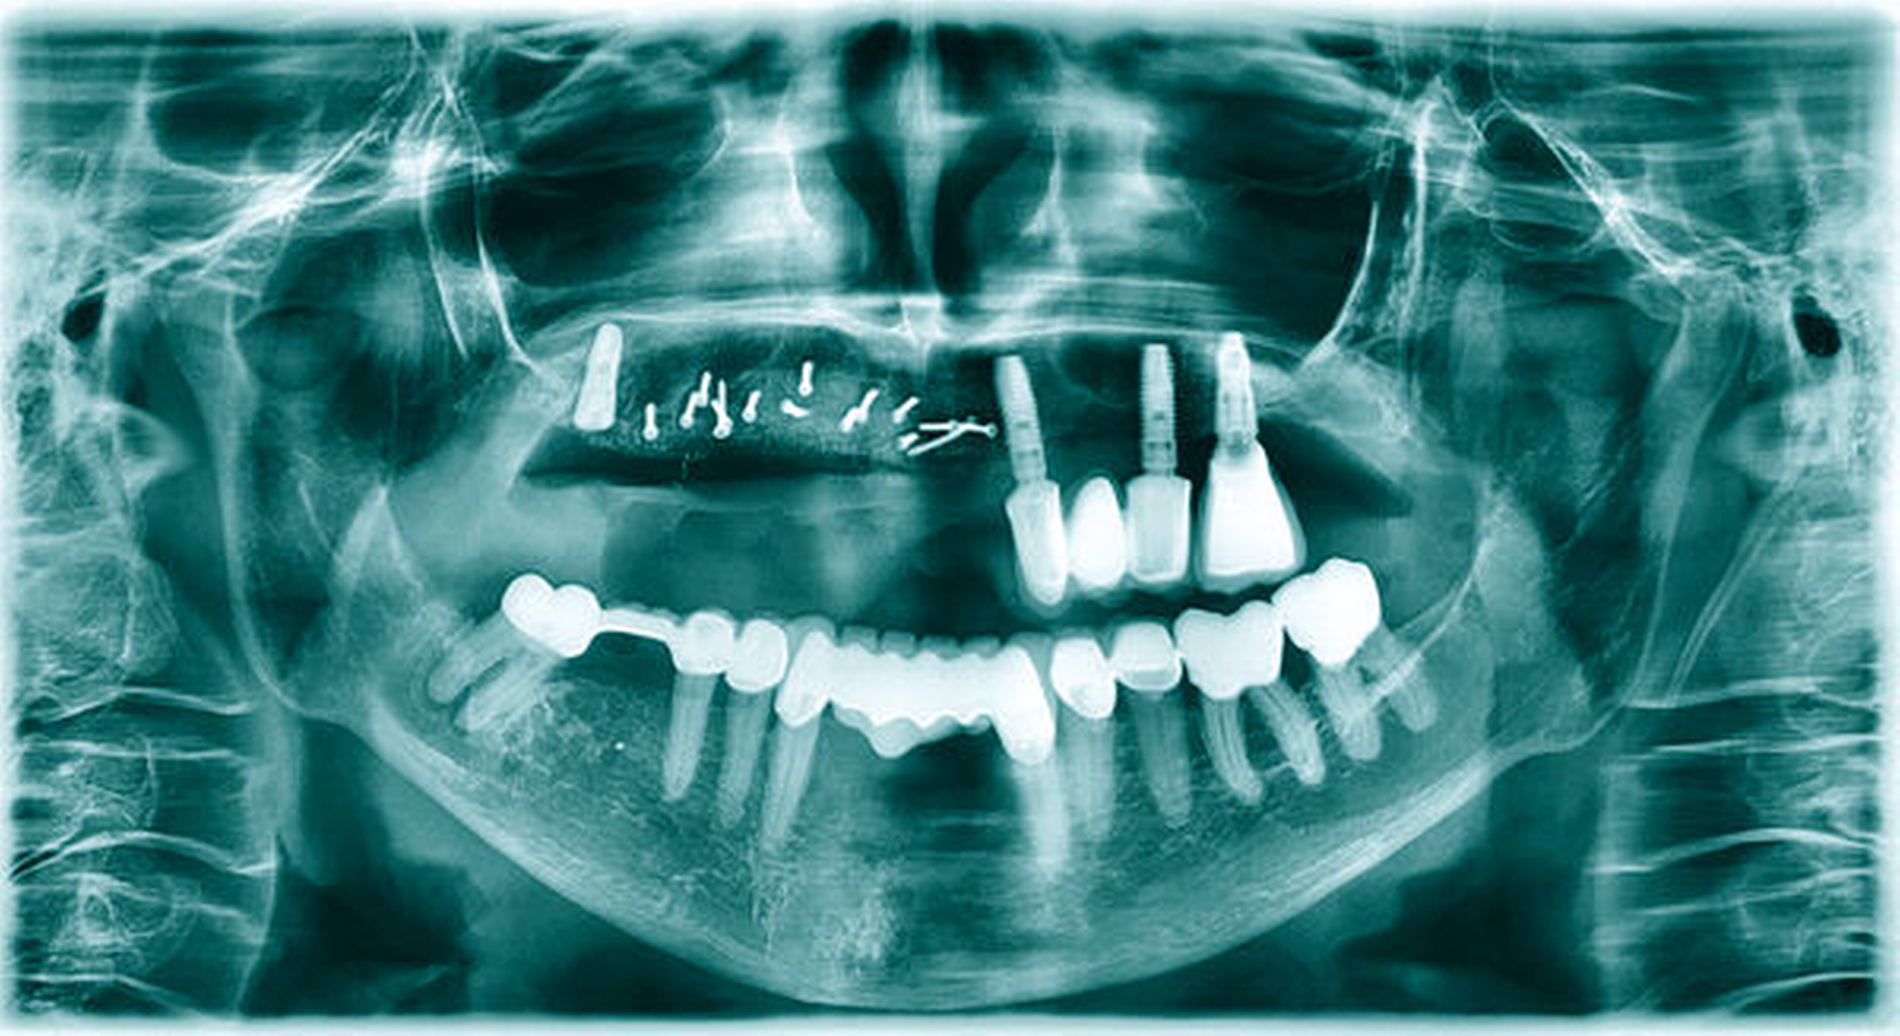

Drei Monate nach Augmentation wurden drei Astra-Tech-EV-Implantate in regio 13, 12 und 22 (jeweils Durchmesser 4,2 mm, Länge 11 mm) nach Entfernung der Osteosyntheseschrauben inseriert sowie das Implantat in regio 16 freigelegt (Abbildung 8). Es zeigten sich dabei stabile knöcherne Verhältnisse mit einer guten Revaskularisation des augmentierten Bereichs. Der Wundverschluss erfolgte analog zu dem bei der Augmentation. Auch hier ergab sich eine ereignislose Wundheilung, so dass die Implantate in regio 13, 12 und 22 nach weiteren drei Monaten freigelegt werden konnten (Abbildung 9). Aufgrund des abgeflachten Vestibulums und der geringen Breite der vestibulären keratinisierten Gingiva erfolgte eine Vestibulumplastik in Kombination mit freien Schleimhauttransplantaten (Abbildung 10).